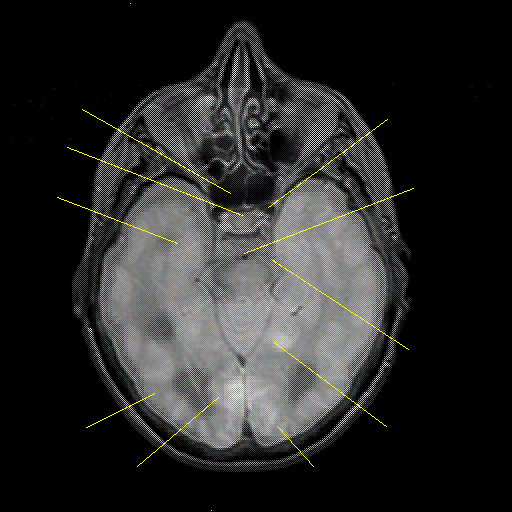

overlay : Slice 20

Slice 20

MRCBFCBF with

Unlabeled

Pointers

Labeled